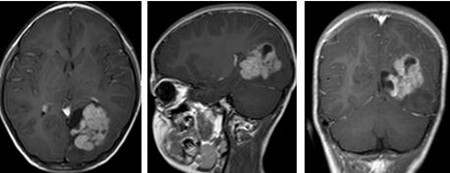

▲术前

为晓霖完善术前检查,小儿神经外科及其团队在全麻下行为晓霖进行“左侧顶枕开颅左枕占位性病变切除术”,术中晓霖的大脑大静脉被保护完好,切除的肿瘤大小约4×4×4cm,术后患儿好转。

术后病理:左枕叶间变性室管膜瘤 WHO III级。